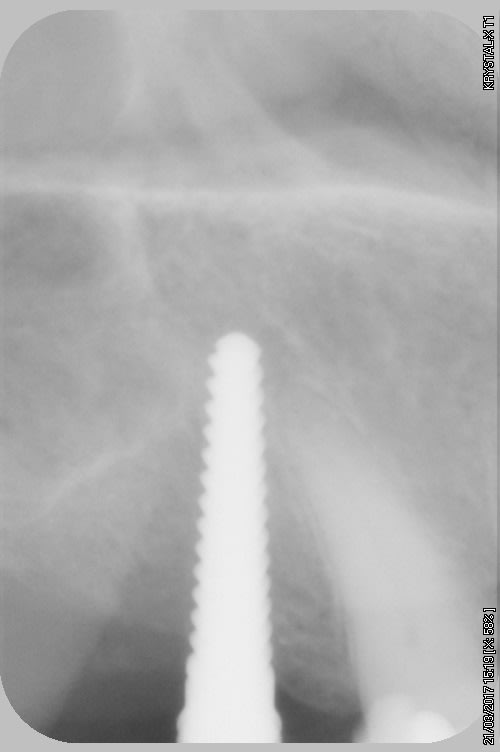

par contre je fais pas mal de radios, exemple spreaders trop près de la racine donc changement d'axe (d'où l’intérêt de l'expansion)

incision crestale lame n°15, tatum, spreader Meissinger implants, PX34120 et OP34100 (summer avec eponges)